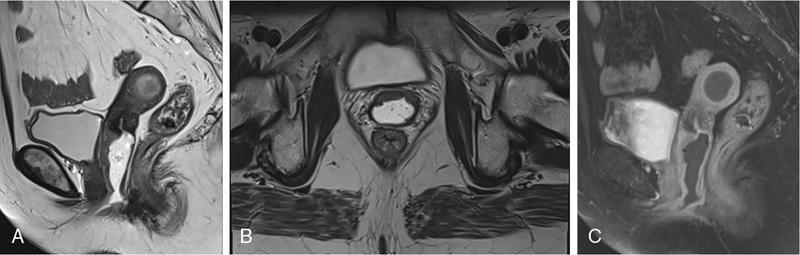

VAGINAL CYSTS Sumeena The vagina is a fibromuscular sheath. Vagina extends from uterus to the vulvar vestibule. The vagina is located in the middle compartment of the pelvis and it is related anteriorly to bladder and urethra, posteriorly to lower rectum and anal canal. The length of vagina ranges from 4 to 12 cm. The posterior wall of vagina is longer and it ends in posterior fornix; the anterior wall is shorter and ends in the anterior fornix. The wall of vagina is composed of three layers: (a) The mucosa consists of nonkeratinized stratified squamous epithelium without glands and its hormone sensitive layer; (b) the muscularis made up of connective tissues and smooth muscle; and (c) the adventitia, which is fascia that connects the vagina to the surrounding pelvic structures and maintains support. The prevalence of vaginal cysts is estimated to be less than 1%. They typically present in the age of 30–40s. Their origin may be Müllerian, Wolffian, squamous or urogenital. Risk factors for vaginal cysts: The vagina may be underevaluated due to probe positioning in routine pelvic US and due to poor vaginal tissue characterization in CT examinations. Though MR imaging provides good tissue characterization, we must focus on the vaginal region to identify any incidental findings. The strengths and limitations of each imaging modality must be understood in assessing the vagina. US is the first-line imaging modality since it is readily available, cost-effective, high resolution and no ionizing radiation. Limitations include operator dependence and patient obesity. The major limitation with transabdominal approach is that the upper portion of the vagina is seen well; the inferior aspect of the vagina is obscured due to shadowing from the pubic symphysis. Limitation with transvaginal US is that the transducer is typically placed in the anterior or posterior fornix which bypasses the perineum and vagina. US imaging needs methodic evaluation performed from introitus to the fornices and include transabdominal, transvaginal and translabial approaches. Due to the poor vaginal tissue characterization and ionizing radiation, CT is usually not indicated for evaluation of the female pelvis. When US is inconclusive, pelvic MR imaging is recommended. The vaginal wall anatomy is best imaged with T2-weighted sequences. The vaginal mucosa has high signal intensity, circular and longitudinal muscle layers have intermediate signal intensity. Embryonic Traumatic Epithelial inclusion cyst/epidermal inclusion cyst/squamous inclusion cyst Skene’s duct cysts Urethral diverticulum Infective Filariasis Vaginitis emphysematosa Epidermoid cyst Sebeceous cyst Endometriotic cyst Ciliated cyst Paraurethral mass Rare Lymphangioma Postradiation Haematocolpos Rectocele and cystocele Prolapsed ectopic ureterocele Large nabothian cyst, tunnel cluster cysts Adenoma malignum Most common type of vaginal cysts, almost up to 40% of cystic masses. As Müllerian epithelial tissue can present anywhere in the vaginal wall, the cysts can also be found anywhere within the vaginal walls. Most common location is along the anterolateral aspect of the vagina. Müllerian cysts present as small, midline cystic masses, with no symptoms and require no treatment. Symptomatic vaginal cysts are treated by excision. The entire cyst wall must be removed to prevent recurrence. Adenocarcinoma can arise in a Müllerian vaginal cyst. The epithelium of Gartner’s cysts is devoid of cytoplasmic mucicarmine and PAS-positive material, in contrast to the epithelium of Müllerian cysts. MRI – Gold standard. Mucus secretion is a unique feature of Müllerian cysts and shows heterogeneous T2 signal. Extent of the cyst, surrounding structures are better evaluated in MRI prior to surgery. Incomplete regression of Wolffian ducts leads to the development of Gartner duct cysts. They are usually noted in the upper anterolateral wall of the vagina above the inferior border of the pubic symphysis. Typically less than 2 cm. When these cysts are large enough, they can compress the urethra causing urinary symptoms. It can also be associated with abnormalities of the metanephric urinary system such as an ectopic ureter, unilateral renal agenesis and renal hypoplasia. USG: Anechoic structure in the upper vagina; transvaginal US provides better differentiation than the transabdominal approach. Fig. 11.19.1.1; T2-axial image shows hyperintense cystic lesions, one in posterior fornix and another one in anterior aspect of upper vagina. Both the lesions are above the level of pubic symphysis. Fig. 11.19.1.2; T2-sagittal image shows hyperintense cystic lesions, one in posterior fornix and another one in anterior aspect of upper vagina. Both the lesions are above the level of pubic symphysis. Bartholin glands are commonly located posterolateral to the vaginal introitus and medial to the labia minora. The obstruction of the gland’s duct either by a stone or a stenosis, which may be caused by prior infection or trauma, leads to Bartholin gland cysts. Cysts are typically round and unilocular, seen at or below the level of the pubic symphysis, usually asymptomatic. This is most apparent on coronal plane imaging. USG: Bartholin gland cysts can be imaged by a transperineal approach. Although these cysts are usually asymptomatic, occasional infection may necessitate drainage of the cysts (Fig. 11.19.1.3). Bartholin gland duct can be obstructed due to stone or stenosis, later which can become infected. The Bartholin’s gland abscess size ranges from 2 to 8 cm with an average of 3 to 4 cm. Antibiotics with or without surgical drainage is the treatment. Marsupialization may be needed in recurrent conditions. USG-complex cystic hypoechoic to anechoic lesions increased throughout transmission. Colour Doppler may show peripheral hyperaemia. Spectral flow – low resistance arterial flow. MRI-T2: Tends to show heterogeneous signal T1 C+ (Gd): pericystic enhancement may be seen (Fig. 11.19.1.4). Vaginal inclusion cysts – also known as epidermal inclusion cysts, most commonly are seen in the distal posterior or lateral vaginal wall at sites of previous trauma or surgery. Inclusion cysts are lined by a stratified squamous epithelium and contain keratinous material. Symptomatic cyst needs treatment. The treatment of choice for symptomatic cysts is marsupialization. MRI-DWI shows restriction (Fig. 11.19.1.5). Skene glands are paired structures in periurethral location near external urethral meatus with ducts draining into the urethra. Skene gland cysts can cause UTI or urethral obstruction. They are distinguished from urethral diverticulum, which are usually midurethral. In T2-weighted images, Skene duct cysts seen as round or oval hyperintense lesions just lateral to the external urethral meatus. MRI:T1 hyperintense due to proteinaceous material. T2 hyperintense. Fluid–fluid level if complicated with debris or haemorrhage (Fig. 11.19.1.6). It may be congenital or result from infection or obstruction. In females, diverticula commonly extends from the posterolateral wall of the mid-portion of the urethra. During voiding cystourethrography (VCUG), they are seen best on postvoid images. Transrectal US shows a cystic mass in proximity to the urethra and it will be seen anterior to the vagina. Lack of radiation and capacity to differentiate solid from cystic masses is the advantage of US over CT. CT shows a periurethral lesion with low attenuation. MRI shows T1 hypointense and T2 hyperintense fluid signal intensity. Postcontrast imaging with gadolinium is used to evaluate infection or inflammation. Adenoma malignum of the cervix is a rare variant of cervical mucinous adenocarcinoma. VAGINAL MALIGNANCIES Rupa Renganathan, Suchana Kushvaha The primary vaginal carcinoma is a very rare gynaecological malignancy and accounts for 2%–3% of genital tract malignancies and 10% of all vaginal malignancies. It is defined as a cancer found in the vagina without histological or clinical evidence of cervical or vulvar malignancy and without previous history of treatment of cancers in the last five years. The commonest primary carcinoma is squamous carcinoma, and other rare primaries are adenocarcinoma, melanoma and sarcomas. The secondaries in the vagina are much more common than the primary and account for more than 80% of vaginal malignancies. Primary vaginal carcinoma is common in elderly, however, seen in the younger women when associated with human papillomavirus (HPV 16 and 18). Vaginal carcinomas are staged based on FIGO classification. Management of the cancer is usually based on the stage of the disease and the histological subtypes. Vagina is an elongated fibromuscular structure connecting the uterus with the vulva. It is approximately 7–9 cm long. The long axis is oriented 90 degrees to the uterine axis and its upper part is oriented almost horizontally and in plane with the pelvic floor. It is lined by the nonkeratinizing stratified squamous epithelium. It has anterior, posterior and lateral walls. The upper portion of vagina is invaginated by the cervix such that a space is created between its walls and the cervix called fornices. The posterior fornix is deeper than the anterior fornix. Anterior wall is separated from the bladder base and the urethra by the anterior vesicovaginal septum while the posterior wall is separated from the rectum by rectovaginal septum. The posterior fornix is covered with the peritoneal reflection that forms the Pouch of Douglas. It is supplied by the vaginal arteries, originating from the internal iliac artery and branches of uterine, middle rectal and inferior vesical arteries. There is considerable overlap in the lymphatics between the various parts of vagina. The upper two-thirds of the vagina drain into the pelvic lymph nodes that include external, internal and common iliac groups and the lower third into the superficial inguinal and femoral lymph nodes. The posterior vaginal wall also drains into the perirectal lymph nodes. MRI is the standard imaging modality for local staging of cancers and also for assessment of treatment response and surveillance due to superior soft tissue resolution, multiplanar capability. In a relaxed state, it is seen as a ‘H’ shaped structure posterior to urethra with the anterior and posterior walls being opposed to each other. The vaginal lumen may have secretions or blood-causing distention of its lumen. The anatomy of the vagina is best depicted on T2w images where three layers of its wall can be distinguished in a nondistended state. The mucosa is T2 hyperintense with a hypointense submucosal and muscularis layer beneath it. It is surrounded by adventitia which is hyperintense due to the venous plexus (Fig. 11.19.2.1A and B). For accurate staging purposes, vagina should be distended with ultrasound gel with the help of a syringe and infant feeding tube (Fig. 11.19.2.1C and D). Before inserting gel, patient consent must be taken and her marital status should be enquired. Care must be taken that air is not insufflated while introducing the jelly. Jelly can also be introduced in patients other than carcinoma vagina in cases where vaginal involvement is suspected in other malignancies. After adequate distention, the walls get separated and the fornices are better delineated. For staging purposes, the vagina is divided into three parts. The upper one-third lies above the level of the bladder base and includes the fornices. The middle one-third is opposite to the bladder base and the lower one-third opposite to the urethra (Fig. 11.19.2.1D). Ultrasound owing to its limited field of view and inaccurate staging is not used for imaging of vaginal pathologies. CT has poor contrast resolution and is used only for lymph nodes staging in known patients of vaginal malignancy. PET CT has the advantage in that it combines both the functional and anatomical information about the tumour. While performing PET for the gynaecological malignancies, general measures to reduce bladder activity, like Foley’s catheterization, IV hydration and diuretic administration, are adapted and the image acquisition is done from the pelvis cranially. The advantage of PET beyond providing functional information is that it provides information about distant metastases. The presence of nodal metastases in patients with vaginal cancers portends a poor prognosis and alters the management. In a study by Christensen et al., PET CT was found to be more sensitive and carried greater negative predictive value as compared to MRI for detection of lymph nodes. However, commonly seen inflammatory and the reactive lymph nodes may show uptake. Node biopsy or excision is mandatory wherever the metastatic involvement is indeterminate or questionable. PET CT is recommended for restaging the recurrent tumour, and differentiating the treatment changes from recurrence in vaginal carcinomas. In cases of vaginal sarcomas, it is used for grading, staging and follow-up imaging. MRI is the main investigation for evaluation of vaginal masses and for both staging and surveillance. Patients are requested to be fasting for at least 4 hours to limit bowel motility and to empty the bladder 1 hour before the study to achieve moderate distention of the bladder. Use of antispasmodic agents like Butylscopolamine 40 mg IM/IV or Glucagon 0.5–1 mg IV/IM can also be considered to reduce bowel movements. The vagina should be distended with about 60 mL of Ultrasound Gel for evaluation of vaginal lesions. The patient is imaged in supine position with phased array abdomino pelvic coil. The saturation band is usually placed anterior and superior to the field of view. T2 imaging remains the mainstay for evaluation of vaginal tumours. The basic sequences for evaluation of vagina lesions are T2 sagittal, axial, coronal and oblique axial, T1 axial and diffusion-weighted imaging in axial plane. The high-resolution oblique axial along the plane of vagina is the best sequence which demonstrates the tumour and its extent. The study may be completed by contrast injection. The sequences for contrast evaluation will include pre-T1 with fat saturation, followed by dynamic contrast injection and postcontrast T1 fat saturated acquisition. The most common clinical presentation would be painless vaginal bleeding (65%–80%) followed by vaginal discharge, pelvic pain, urinary symptoms and mass being felt in the vagina. The primary carcinoma are usually squamous cell carcinoma and accounts for about 80% of cases. They are more commonly seen in the upper third in the posterior wall. It is associated with HPV and about 30% of women also have history or associated intraepithelial and invasive cancers of cervix and vulva. About a third of patients present with lymph nodal metastasis in the pelvis or inguinal region at the time of clinical presentation. Adenocarcinoma accounts for only 9% of primary vaginal malignancies, and they are usually seen in the anterior wall of the upper third of the vagina. They affect younger age group (14–21 years) and arise from the lesions such as endometrial deposits and the vaginal adenosis. About two-thirds of the cases have exposure to Diethylstilbestrol to their mothers. When seen in older women, they are usually clear cell carcinomas. Staging of vaginal carcinoma with MRI parallels clinical FIGO staging (Figs 11.19.2.2–11.19.2.4). The tumour is best seen on T2-weighted sequences where it is seen as an intermediate signal (higher than muscle and lower than fat). Adenocarcinomas typically exhibit high T2 signal. Because of the signal on T2, the tumour is well delineated from the vaginal wall which displays low signal intensity. When the tumour is limited to vagina, it is difficult to be seen on T1 sequences unless it causes a contour abnormality as the tumour will be isointense on T1. Stage I tumours are those which are either seen as mass/plaque like thickening but will be limited to vagina and will be diagnosed if the hypointense T2 signal of the vaginal wall is preserved (Fig. 11.19.2.5). When the tumour disrupts this hypointense layer and extends into the paravaginal fat, the staging becomes Stage II (Fig. 11.19.2.6). The loss of normal signal of the vaginal wall should be looked at all three orthogonal planes to identify subtle loss of the signal which is the important finding which upstages the tumour.